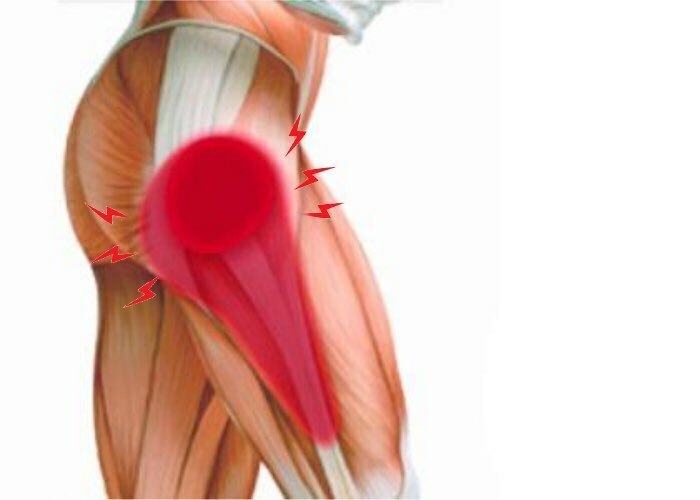

Здоровье суставов: Трохантерит и его влияние на мышцы